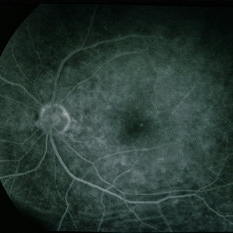

BRVO - Massive Exudate from Collaterals

Feb 24 2014 by David Callanan, MD

66-year-old female with BRVO - massive exudate from collaterals, 20/70 OD; 20/25 OS in 1985; +HTN, glaucoma; 20/200 OD 1987.

Condition/keywords: branch retinal vein occlusion (BRVO), collaterals, exudate